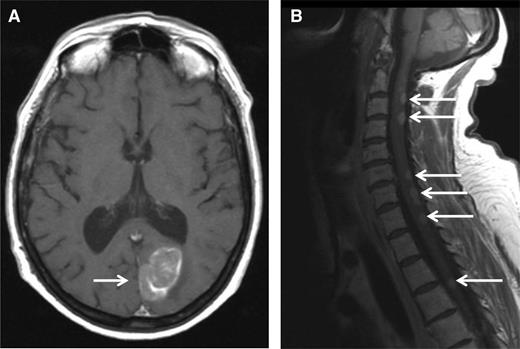

A 51-year-old woman was diagnosed with IgA-κ MM in 2004. At this time, she presented with symptomatic myeloma-related bone lesions, and a bone marrow aspirate confirmed the presence of 33% PCs. The International Scoring System (ISS) score was low (I), and a fluorescence in situ hybridization (FISH) analysis did not reveal any adverse cytogenetic factors (t[4;14] translocation, 17p deletion, and t[14;16] translocation). The first line of therapy consisted of 4 cycles of vincristine-adriamycin-dexamethasone followed by high-dose melphalan/ASCT. The patient achieved a complete remission (CR) after the completion of therapy, but the disease relapsed only 6 months after transplantation. At this time, the patient was treated with a regimen consisting of bortezomib-thalidomide-dexamethasone. During the fifth cycle of bortezomib-thalidomide-dexamethasone, she developed progressive ataxia, and an MRI scan revealed a paramedian occipital lesion (3.6 × 2 cm), as well as multiple posterior lesions of the medulla from C2 to T6 (Figure 1). A CSF analysis revealed the presence of 30 leukocytes per mm3, 80% of which were clonal PCs. At the same time, the percentage of bone marrow PCs was <5%, and no M-component was present in serum or urine. Therefore, we arrived at the diagnosis of a relapsed CNS EMM. The patient then started lenalidomide (25 mg/d, days 1-21) plus high-dose dexamethasone (40 mg/d, days 1-4; days 15-18) (Len-Dex) therapy in combination with cranial irradiation (30 grays) plus intrathecal (IT) injections of methotrexate (15 mg), cytarabine (40 mg), and hydrocortisone (20 mg) until the disappearance of PCs from the CSF (5 IT injections total). The clinical evolution was favorable with the disappearance of neurologic symptoms and the disappearance of both MRI lesions and CSF abnormalities. The patient continued to receive Len-Dex therapy, but the disease recurred after cycle 12 with the same CNS involvement. At that point, treatment was discontinued, and the patient died 3 weeks later.

MRI. MRI (T1 weighted) showing an occipital mass with leptomeningeal involvement (A, white arrow) and multiple posterior medullary lesions (B, white arrows), in a relapsed MM patient who developed progressive ataxia.

CNS involvement is uncommon and observed in ∼1% of MM patients.35,36 Retrospective studies highlight an extremely poor prognosis for CNS EMM with a median overall survival of <6 months.35-39 Any neurologic symptom presented by an MM patient should raise the possibility of the presence of CNS EMM. However, alternative diagnoses should be considered (eg, hypercalcemia, hyperviscosity, spinal cord compression, CNS infection, and peripheral neuropathy). MRI is the most sensitive imaging method to detect leptomeningeal infiltration. In the present case, MRI findings were strongly in favor of CNS EMM. CSF analysis is mandatory and should include the clonal characterization of PCs using both cytology and flow cytometry. FISH analysis of PCs from CSF is usually technically difficult. CSF analysis should also include protein measurement including IT M-component characterization by electrophoresis and immunofixation. Bacterial, viral, fungal, and/or parasitic screening should be considered for differential diagnosis. In the present case, the diagnosis was confirmed by the presence of clonal PCs in the CSF. Proving the diagnosis of CNS EMM can be challenging. For example, in case of an encephalic lesion detected by MRI along with an inconclusive CSF analysis, a surgical biopsy should be considered. However, the risk of the procedure has to be balanced with patient age, performance status, and the therapeutic impact. In addition, in case of a specific CNS-involvement symptom such as numb chin syndrome, we generally retain the diagnosis of CNS EMM, even if both MRI and the CSF analysis are not confirmative. Although the therapy of CNS EMM is difficult, the present case illustrates that a durable response can be achieved by using both systemic and CNS-specific therapy. Systemic CNS EMM therapy should ideally include drugs that may cross the blood-brain barrier (BBB). In addition to high-dose corticosteroids, thalidomide and lenalidomide have been reported to penetrate the BBB in nonhuman primates.40 In patients, thalidomide has been shown to cross the BBB.41 The third-generation IMiD pomalidomide has demonstrated a good penetrance of the BBB in a murine model.42 Notably, a durable CSF remission was recently reported using a pomalidomide-dexamethasone treatment.43 Of course, the ability of IMiDs to treat CNS myeloma should be evaluated in a larger number of patients, ideally in the context of prospective trials. With the exception of marizomib (in rodents),44 there is no clear evidence that PIs have the ability to cross the BBB. Alkylating agents (cyclophosphamide or melphalan) penetrate the CSF poorly. Other conventional chemotherapies known to cross the BBB (high-dose methotrexate or cytarabine) are not effective in treating MM. However, durable responses have been reported using bendamustine in combination with thalidomide.45 In addition to systemic anti-MM therapy, CNS irradiation and IT chemotherapy have been shown to improve the duration of response.35,37,38 Regarding CNS irradiation, both cranial and cranio-spinal irradiation are reported in the literature. However, larger and homogeneous series are needed to determine the best strategy. Overall, we recommend treating CNS EMM with the combination of (1) a systemic anti-MM regimen that crosses the BBB (ideally an IMiD-dexamethasone–based therapy), (2) CNS irradiation, and (3) IT chemotherapy until the disappearance of PCs from the CSF.